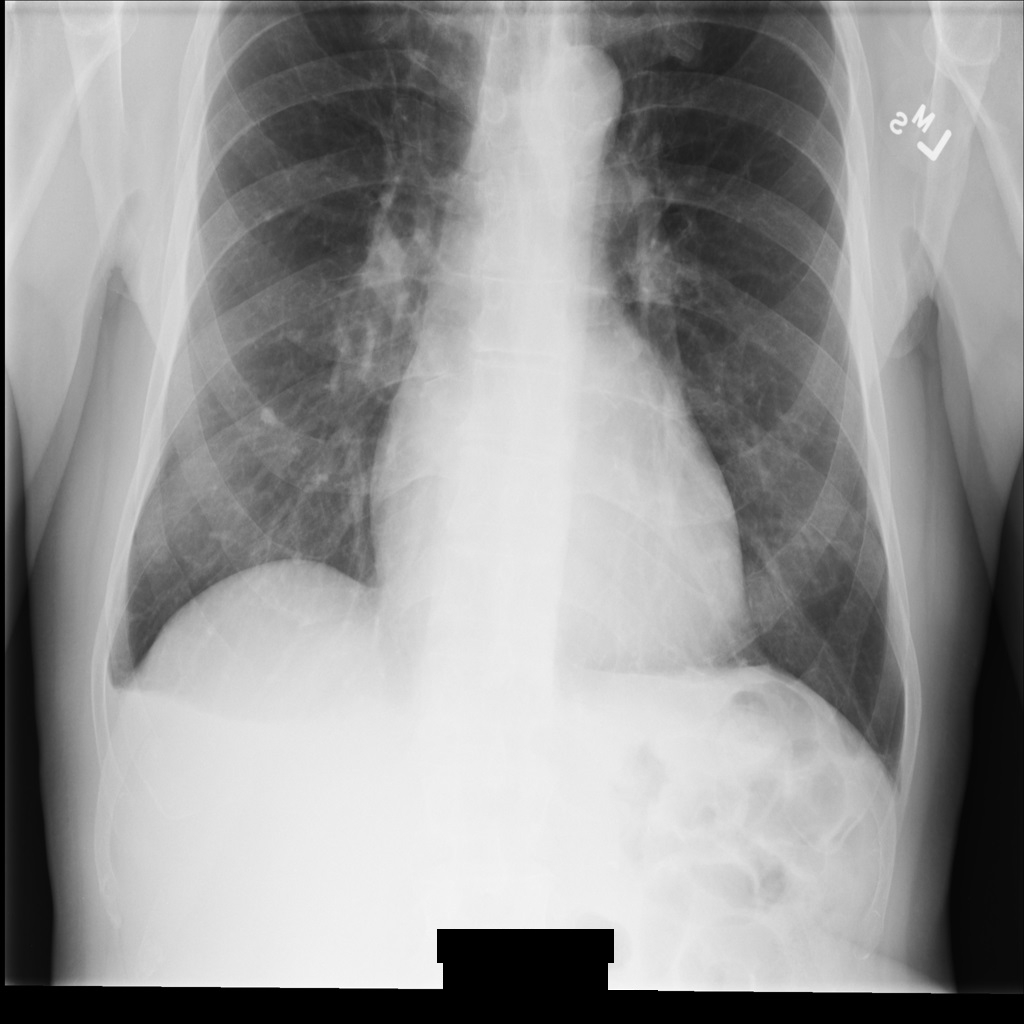

샘플 이미지

이 페이지의 일부 샘플에는 익명화된 이미지의 출력이 포함되어 있습니다. 각 샘플은 다음과 같은 원본 이미지를 입력으로 사용합니다. 각 익명화 작업의 출력 이미지를 이 원본 이미지와 비교하여 작업의 효과를 확인할 수 있습니다.